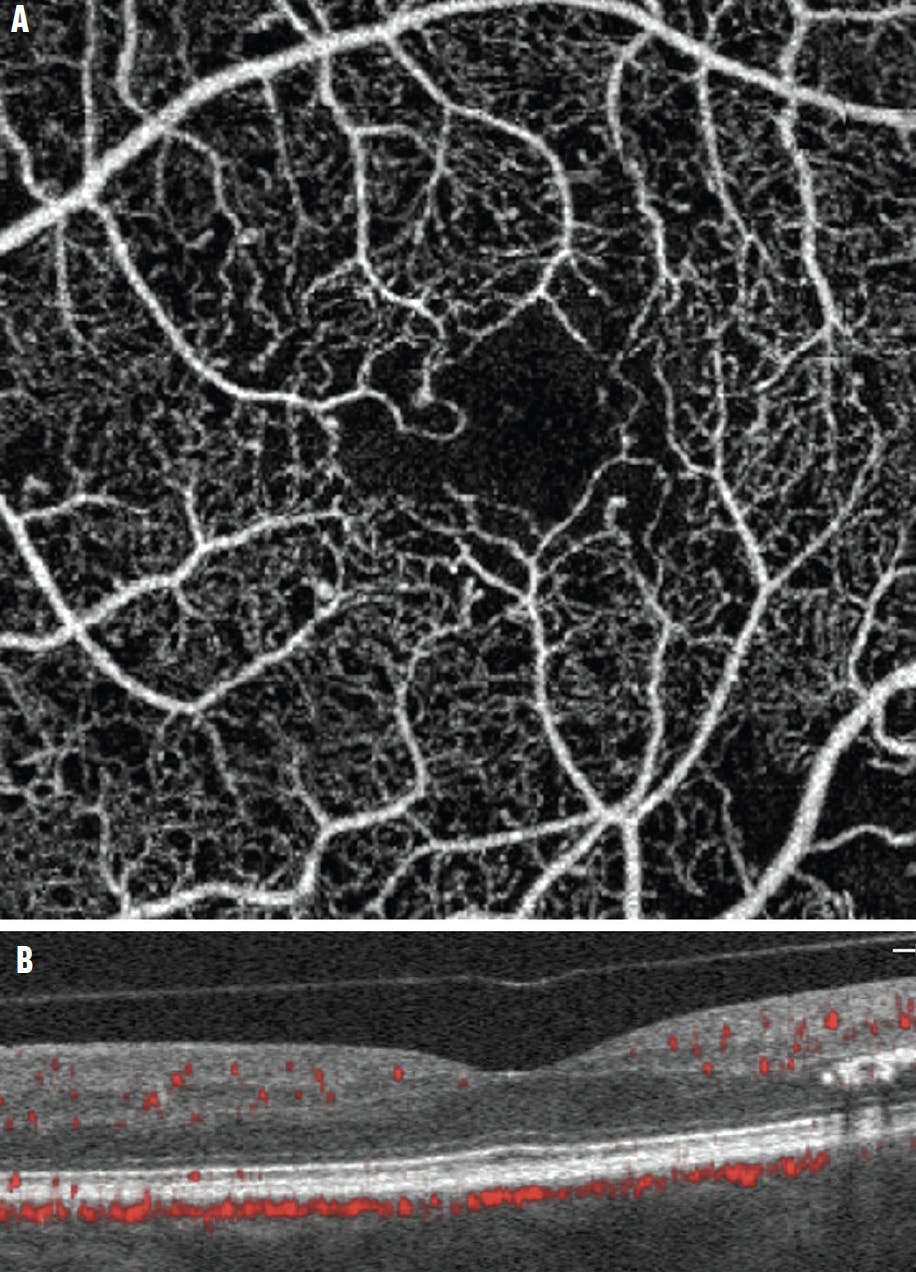

<p>Figure 2. The full-thickness en face OCTA of the eye of a 36-year-old woman with type 1 diabetes showed an irregular, enlarged foveal avascular zone (FAZ) due to nonperfusion (A). Note the relatively normal retinal appearance on the OCT B-scan with flow overlay (B). In general, the full-thickness OCTA slab is the best approach for outlining the entire FAZ.</p>

Figure 2. The full-thickness en face OCTA of the eye of a 36-year-old woman with type 1 diabetes showed an irregular, enlarged foveal avascular zone (FAZ) due to nonperfusion (A). Note the relatively normal retinal appearance on the OCT B-scan with flow overlay (B). In general, the full-thickness OCTA slab is the best approach for outlining the entire FAZ.